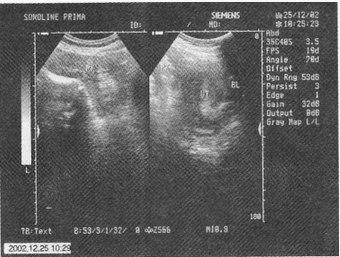

男性,72岁,有血吸虫疫区接触史;上腹胀痛,腹膨隆.

腹部彩超检查图片